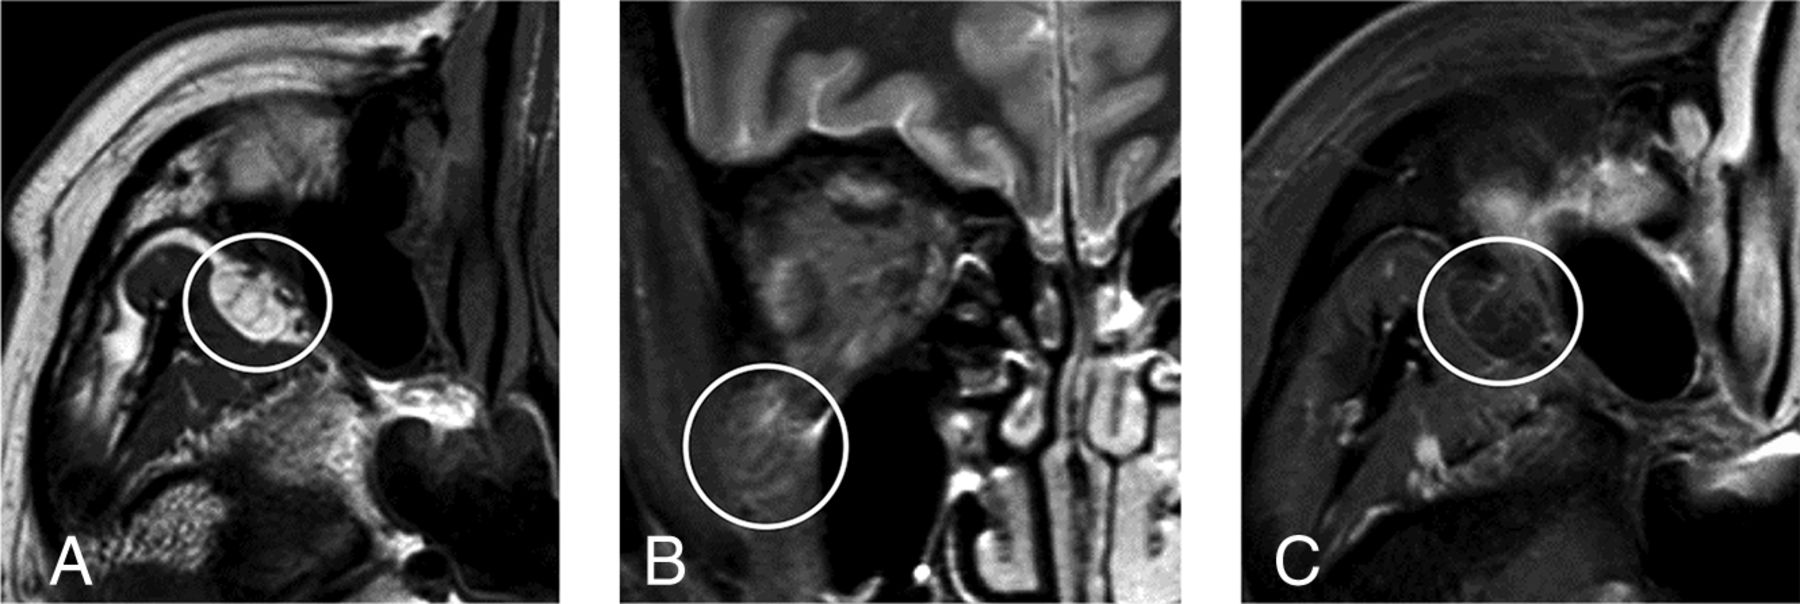

Prolapse was defined as present when a discrete, rounded focus of fat signal intensity could be identified as both distinguishable from the normal infratemporal fossa fat and contiguous with the normal orbital fat via the inferior orbital fissure (Fig 1). When prolapse was present, 1 fellowship-trained neuroradiologist performed a long-axis measurement of the prolapsed fat on high-resolution T1 images. The same neuroradiologist also evaluated the prolapsed fat for associated septa on T1-weighted images, fluid signal on STIR images, and enhancement on gadolinium-enhanced T1-weighted images with fat suppression (Fig 2). Additionally, a different neuroradiologist measured the perpendicular distance from the anterior margin of each globe to the interzygomatic line with the upper limit of normal defined as 21 mm7 and the lower limit of normal defined as 12 mm.8

Axial T1-weighted image (A) demonstrates septa within the prolapsed orbital fat (circle). Coronal STIR image (B) demonstrates faintly increased fluid signal associated with the prolapsed orbital fat (circle). Axial gadolinium-enhanced T1-weighted image with fat suppression (C) demonstrates faint enhancement associated with the prolapsed orbital fat (circle).